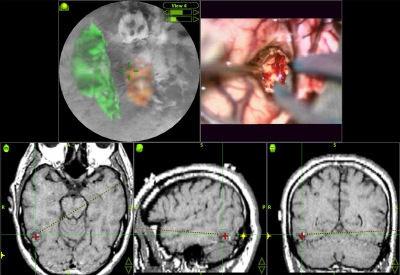

Intraoperative navigation

Intraoperative navigation uses both preoperative images (CT and MR) and intraoperative images (ultrasound and video) to provide localization information during surgery. The main challenge involved in surgical navigation is the registration of the preoperative data with the surgical environment -- that is, with the patient and the surgical instruments. Until now, the usage of 3D imaging during surgery has been limited due to the lack of computation power needed to produce real-time images.

Today, numerous systems augment the surgeon's vision during surgery by providing for the real-time fusion of preoperative volumetric data with intraoperative data, such as video, ultrasound, and images from a surgical microscope and endoscope. Other systems enhance intraoperative visualization by providing feedback regarding the location of the surgical instruments with respect to preoperative data. They use optical or mechanical sensors to localize instruments in the operating room, then map them onto the preoperative images (see figure 7, below).

![]() |

| Figure 7 |